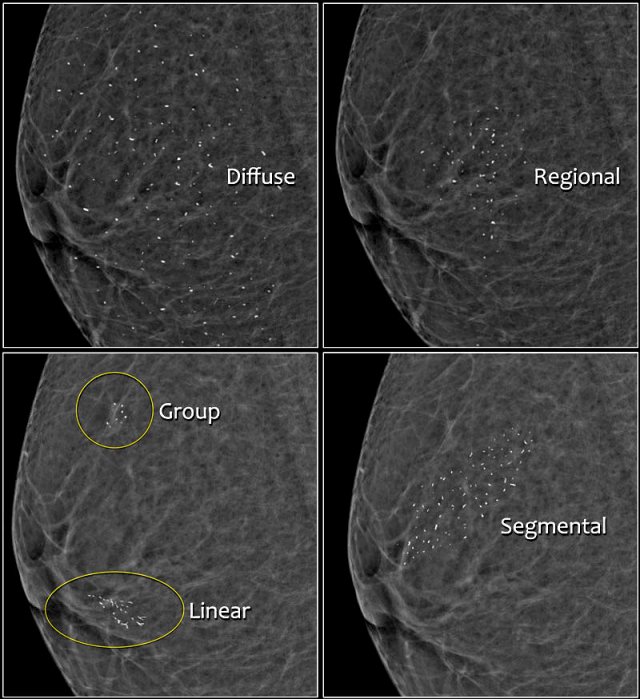

Distribution of calcifications

The arrangement of calcifications, the distribution, is at least as important as morphology.

These descriptors are arranged according to the risk of malignancy:

1. Diffuse: distributed randomly throughout the breast.

2. Regional: occupying a large portion of breast tissue > 2 cm greatest dimension

3. Grouped (historically cluster): few calcifications occupying a small portion of breast tissue: lower limit 5 calcifications within 1 cm and upper limit a larger number of calcifications within 2 cm.

4. Linear: arranged in a line, which suggests deposits in a duct.

5. Segmental: suggests deposits in a duct or ducts and their branches.

The 2013 edition refines the upper limit in size for grouped distribution as 2 cm (historically 1 cm) while retaining > 2 cm as the lower limit for regional distribution.